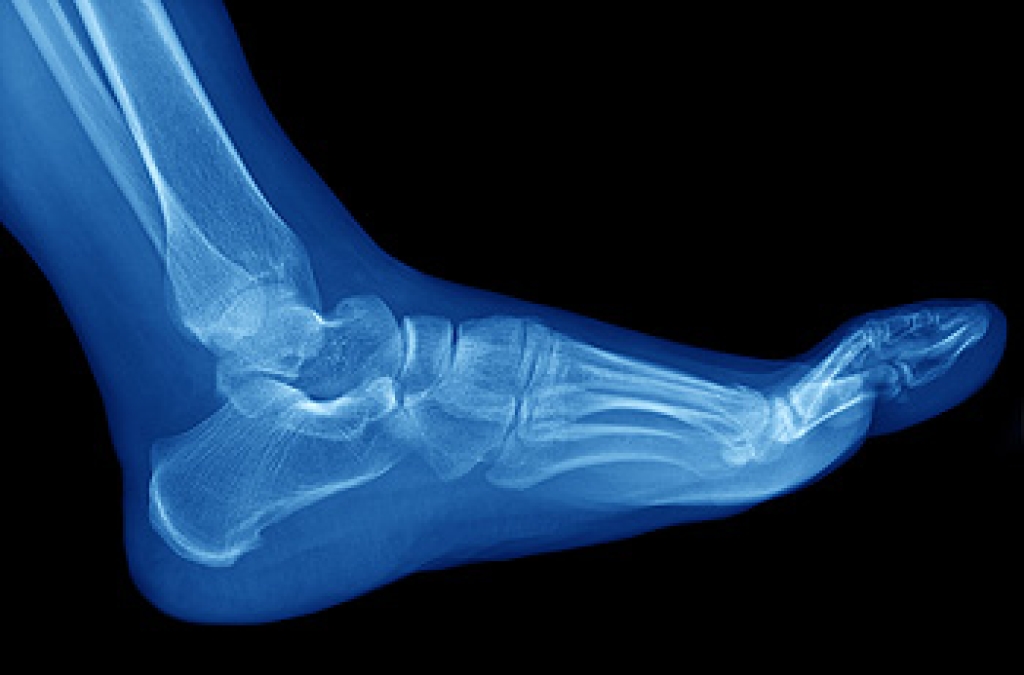

People who enjoy running are generally aware of the importance of having strong and stable feet. This can be accomplished by frequently performing stretching techniques that are designed to keep the feet flexible and strong. The feet are comprised of different types of muscles. Shorter muscles are known as intrinsic muscles, and are found inside the foot. They are responsible for moving the feet, and providing stability. A simple and effective movement known as toe curling can help to improve overall foot function. Additionally, the toes may become stronger when an effort is made to keep the big toe on the floor while lifting the other toes. Research has indicated the ankle will benefit when heel lifts are performed. If you would like more information about the importance of stretching the feet, or suggestions on specific foot stretches, please consult with a podiatrist.

Being the backbone of the body, the feet carry your entire weight and can easily become overexerted, causing cramps and pain. As with any body part, stretching your feet can serve many benefits. From increasing flexibility to even providing some pain relief, be sure to give your feet a stretch from time to time. This is especially important for athletes or anyone performing aerobic exercises, but anyone experiencing foot pain or is on their feet constantly should also engage in this practice.